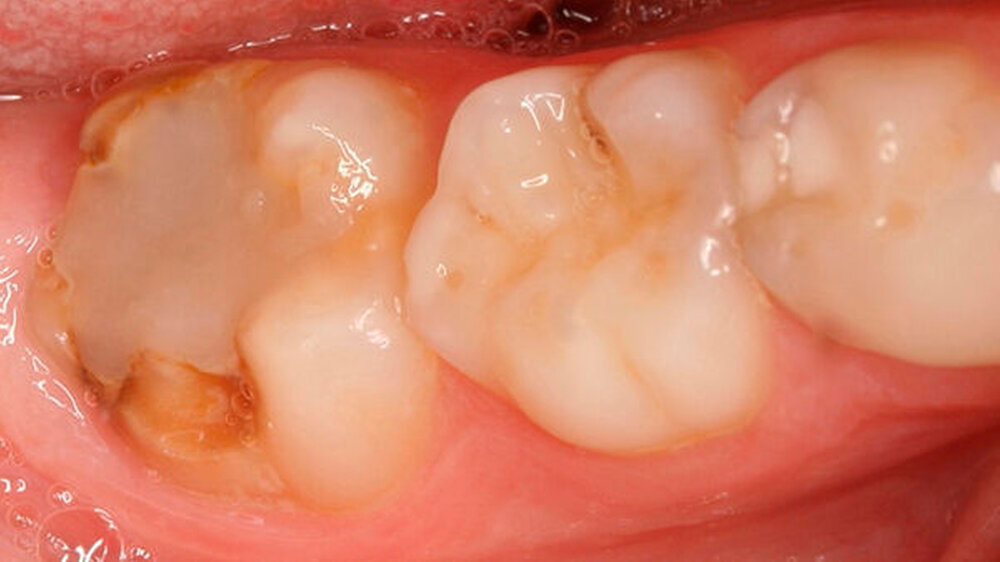

Mit dem Durchbruch der ersten bleibenden Molaren treten dann bisher unbekannte Beschwerden auf wie zum Beispiel eine übermäßig ausgeprägte Kälte-/Wärmeempfindlichkeit. Für manche Kinder wird dadurch nicht nur die Mundhygiene sondern auch die Nahrungsaufnahme erschwert. Zusätzlich bricht oft schon in der Durchbruchs-Phase der Schmelz ein (Abbildung 1), was die Überempfindlichkeit in teils akute Zahnschmerzen übergehen lässt.

Bei einigen Patienten bestand allerdings auch schon im Milchgebiss eine Neigung zu Hypomineralisationen (Abbildung 3), klassifiziert wurden diese inzwischen als MDH (=deciduous molar hypomineralization) [Elfrink et al., 2012]. Inwiefern eine Hypomineralisation im Milchgebiss aber tatsächlich einen Indikator für eine MIH im bleibenden Gebiss darstellt, ist bisher nicht genauer zu beschreiben [Elfrink et al., 2012].

Die Behandlung der MIH stellt an Patienten und Behandler dadurch ganz besondere Herausforderungen, denn zu der Schmerzempfindlichkeit/Überempfindlichkeit der Zähne kommt die in der Regel schlechte Anästhesierbarkeit der betroffenen Zähne hinzu [Steffen & van Waes, 2011]. Die Behandlungsnotwendigkeit im Durchbruch erschwert das Kavitätendesign, die Trockenlegung und die Wahl des Füllungsmaterials erheblich [Lygidakis et al., 2010]. Aber auch nach vollständigem Durchbruch bleibt die Frage des Kavitätendesigns und der erforderlichen Restauration bestehen [Lygidakis et al., 2010].